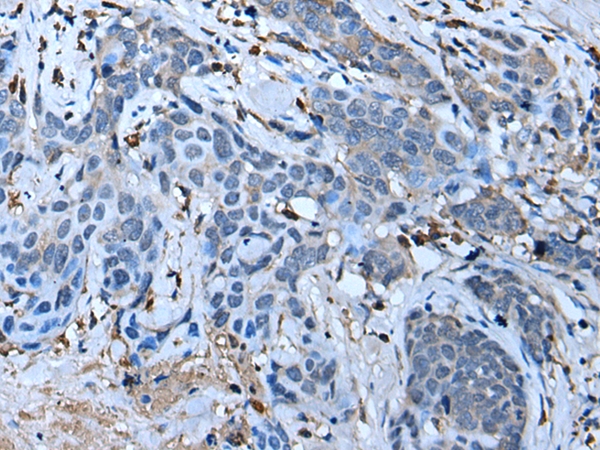

IHC positive control: |

Human thyroid cancer |

ELISA, IHC |